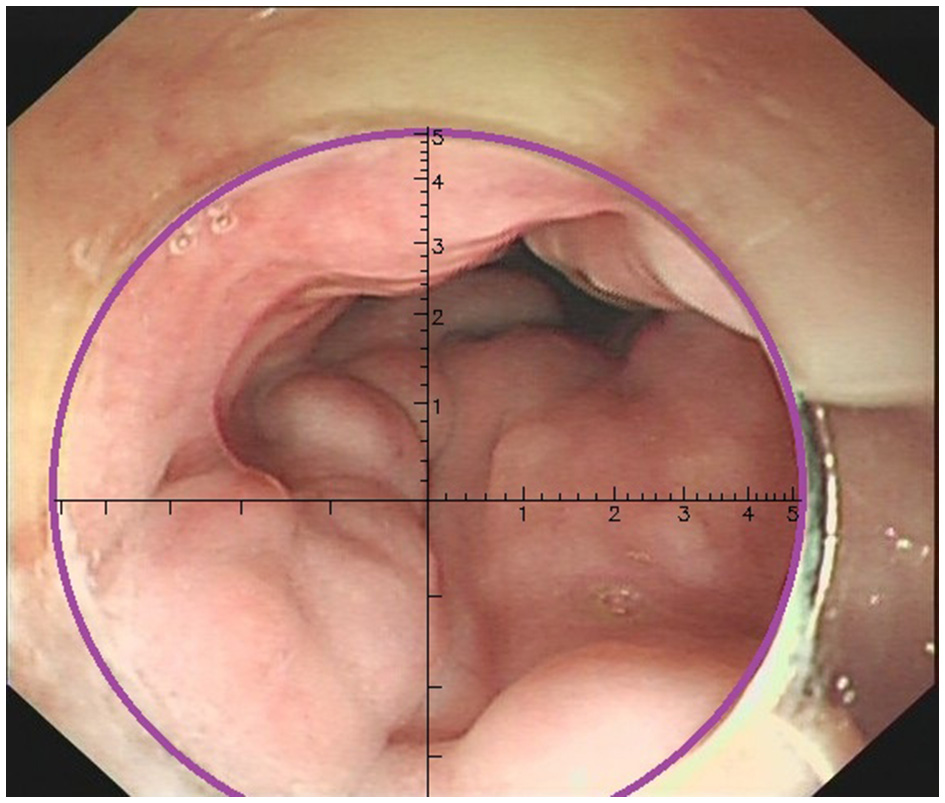

Three physicians, each with over 10 years of endoscopic experience and having performed more than 100 EVL cases, conducted a comprehensive review of the endoscopic features, videos, and images of all cases. They made meticulous observations and precise measurements using EVR. The endoscopic videos and images of all patients were incorporated into the EVR to measure and record the diameter of the largest vessel. EVR is an AI-assisted technique that connects a transparent cap with an inner diameter of 1 cm to the front end of the endoscope to use as a reference. EVR is constructed using algorithms, such as Gaussian filters, Canney Edge detector and Hove circles. Notably, EVR was corrected using a barrel deformation experiment. When approaching the target EV, the discontinuous arc of the cap was detected using AI, and a Cartesian coordinate system was subsequently established in the center of a circle corresponding to the arc (Figure 2). The diameter of EV was determined using the aforementioned coordinate system, and EV size was obtained through reading the scale on a ruler. Retrospective data analysis was performed using EVR software to detect the diameter of EV in endoscopic videos or images. Notably, each endoscopy video used was the original, with a tip cap at the front end of the endoscope. For EV with a diameter >1 cm, the secondary mode of EVR was used. The distance between the anterior cap of the endoscope and the blood vessel was evaluated using the multiplication method to obtain the EV diameter, and this was calculated according to a 1:2 ratio, where a diameter of 2 cm is displayed as 1 cm in EVR. One case of EVR measurement of the variceal diameter by images is displayed in Figure 3. One case of EVR measurement of the variceal diameter by videos is displayed in Supplementary Video 1.

Figure 2

The end of the transparent cap was marked as a discontinuous arc in the endoscopic field of view (purple arc on the figure). When the artificial intelligence recognized the arc, it automatically formed a coordinate system.

Figure 3

Measurement of the EV diameter using EVR by images. The variceal diameter of the patient was about 0.6 cm.